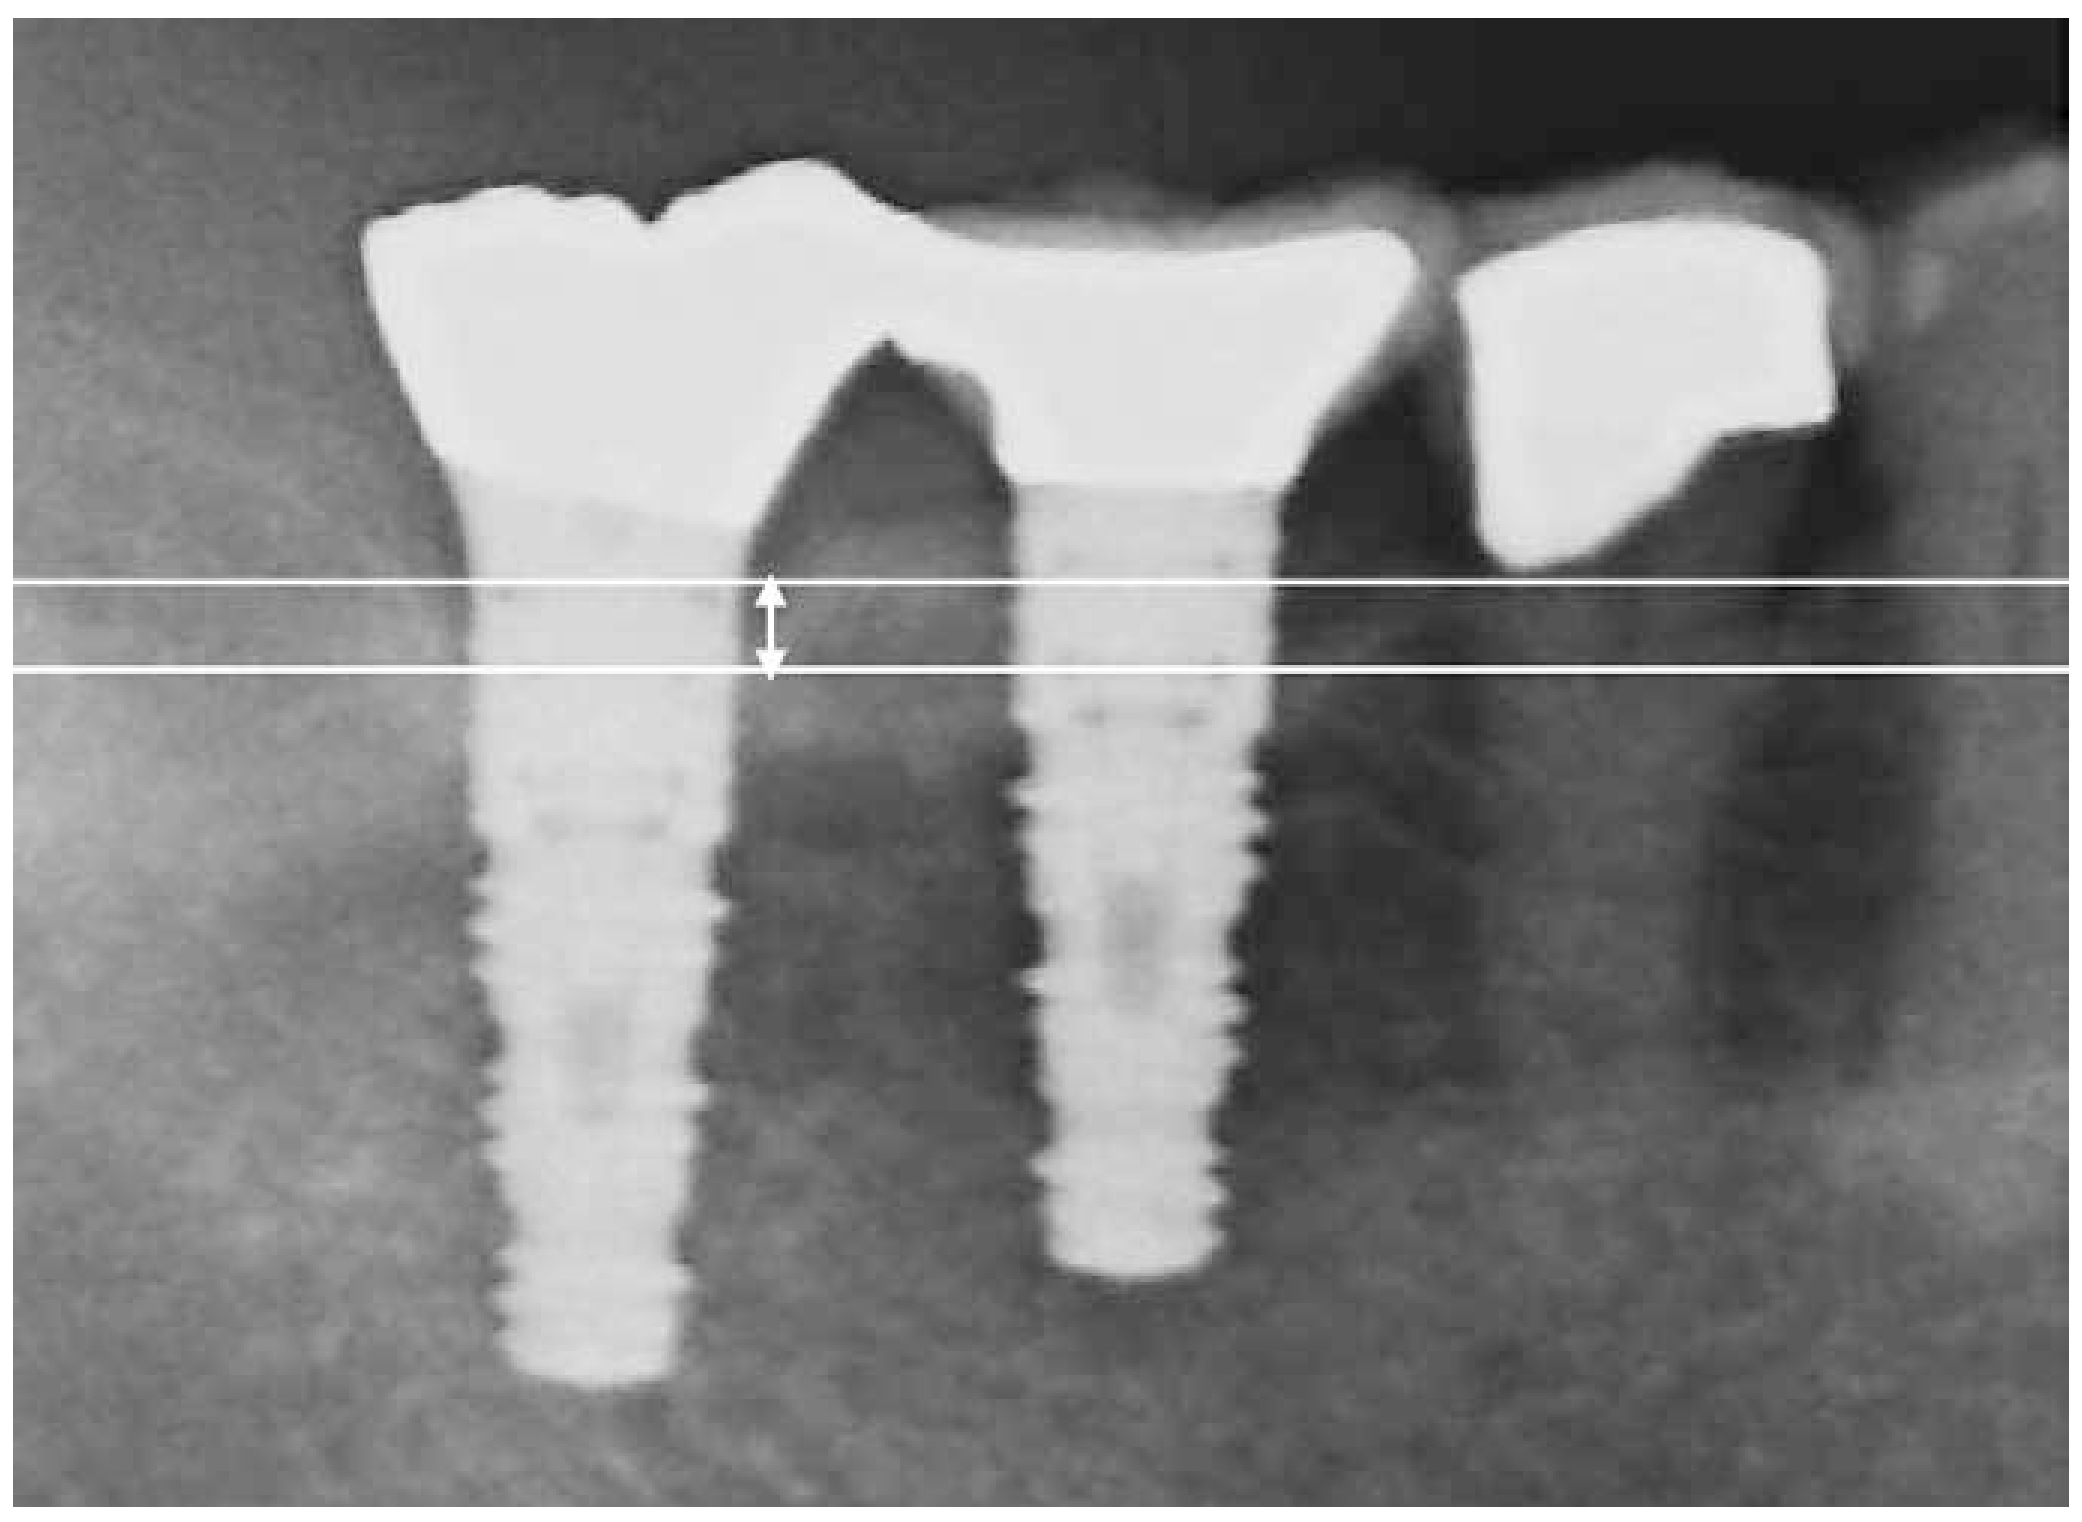

Radiographic images were acquired using either a dental X-ray unit with a long-cone paralleling technique or a panoramic radiograph. Bone volume was calculated by measuring the distance from the marginal bone level to the implant apex (a), and the implant length (b). The ratio of (b/a) was used to estimate relative bone volume. Baseline bone volume was defined as the radiographic measurement taken one year after prosthetic loading. The difference between baseline and current bone volume was defined as marginal bone loss.7,8 (Figure 1: Criterion 1). Alternatively, as Criterion 2, the vertical distance from the marginal bone crest to the base of the intrabony defect was measured as the bone defect depth (Figure 2: length of white arrow).

Fig 2

(Fig.2) Criterion 2.The white arrow indicates the amount of bone loss, defined as the distance from the bone crest to the base of the bone defect.